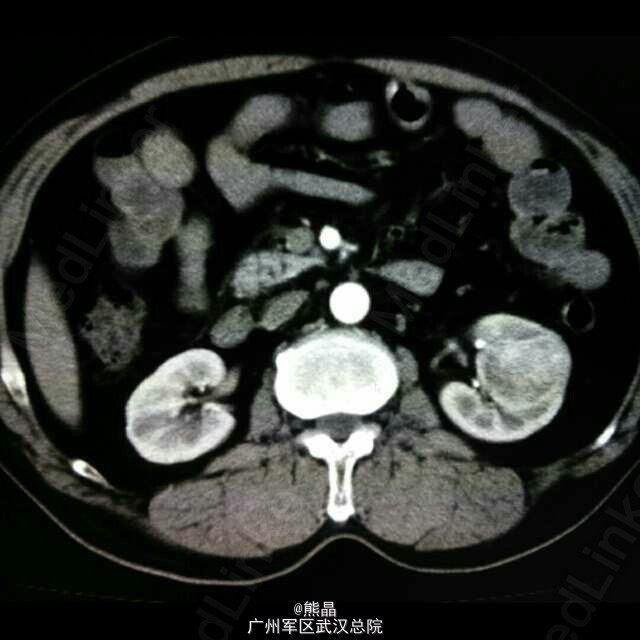

患者男性,61岁,体检发现左肾占位病变5天,无明显临床症状。 肾脏嗜酸性细胞瘤是一种少见的肾脏良性肿瘤,与肾癌鉴别较困难。 肾脏嗜酸性细胞瘤增强扫描可以出现轮辐状强化,是其特征之一,肿瘤中可见星状瘢痕,为纤维母细胞增生,如肿瘤中有钙化,可以除外嗜酸。